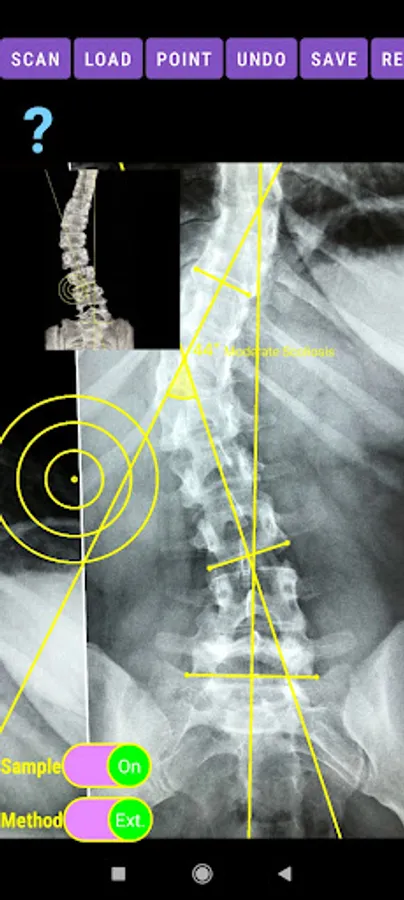

-Offers a very convenient way to determine the most accurate possibly way at once. By marking four points at the same X-ray, at each spine the App calculates the Cobb angle. In cases where values are out of normal ranges, the scoliosis is categorized according to measured angle as mild, moderate, severe. To simplify the process and to minimize inter-observer errors usually by not selecting the actual end vertebra, the app offers also in ext mode the ability to draw the vertical reference line through the patient’s sacrum and to identify more easily the end vertebrae (ext method).

The app offers a very convenient way to asses spinal deformity by measuring the Cobb angle. The first thing is to load one image from your photo library or capture a photo from x-rays photos of a patient. The app offers two measuring methods, the simple (Sim.) and the extended (Ext.). By clicking the relevant option, the option is highlighted and the respective method is activated.